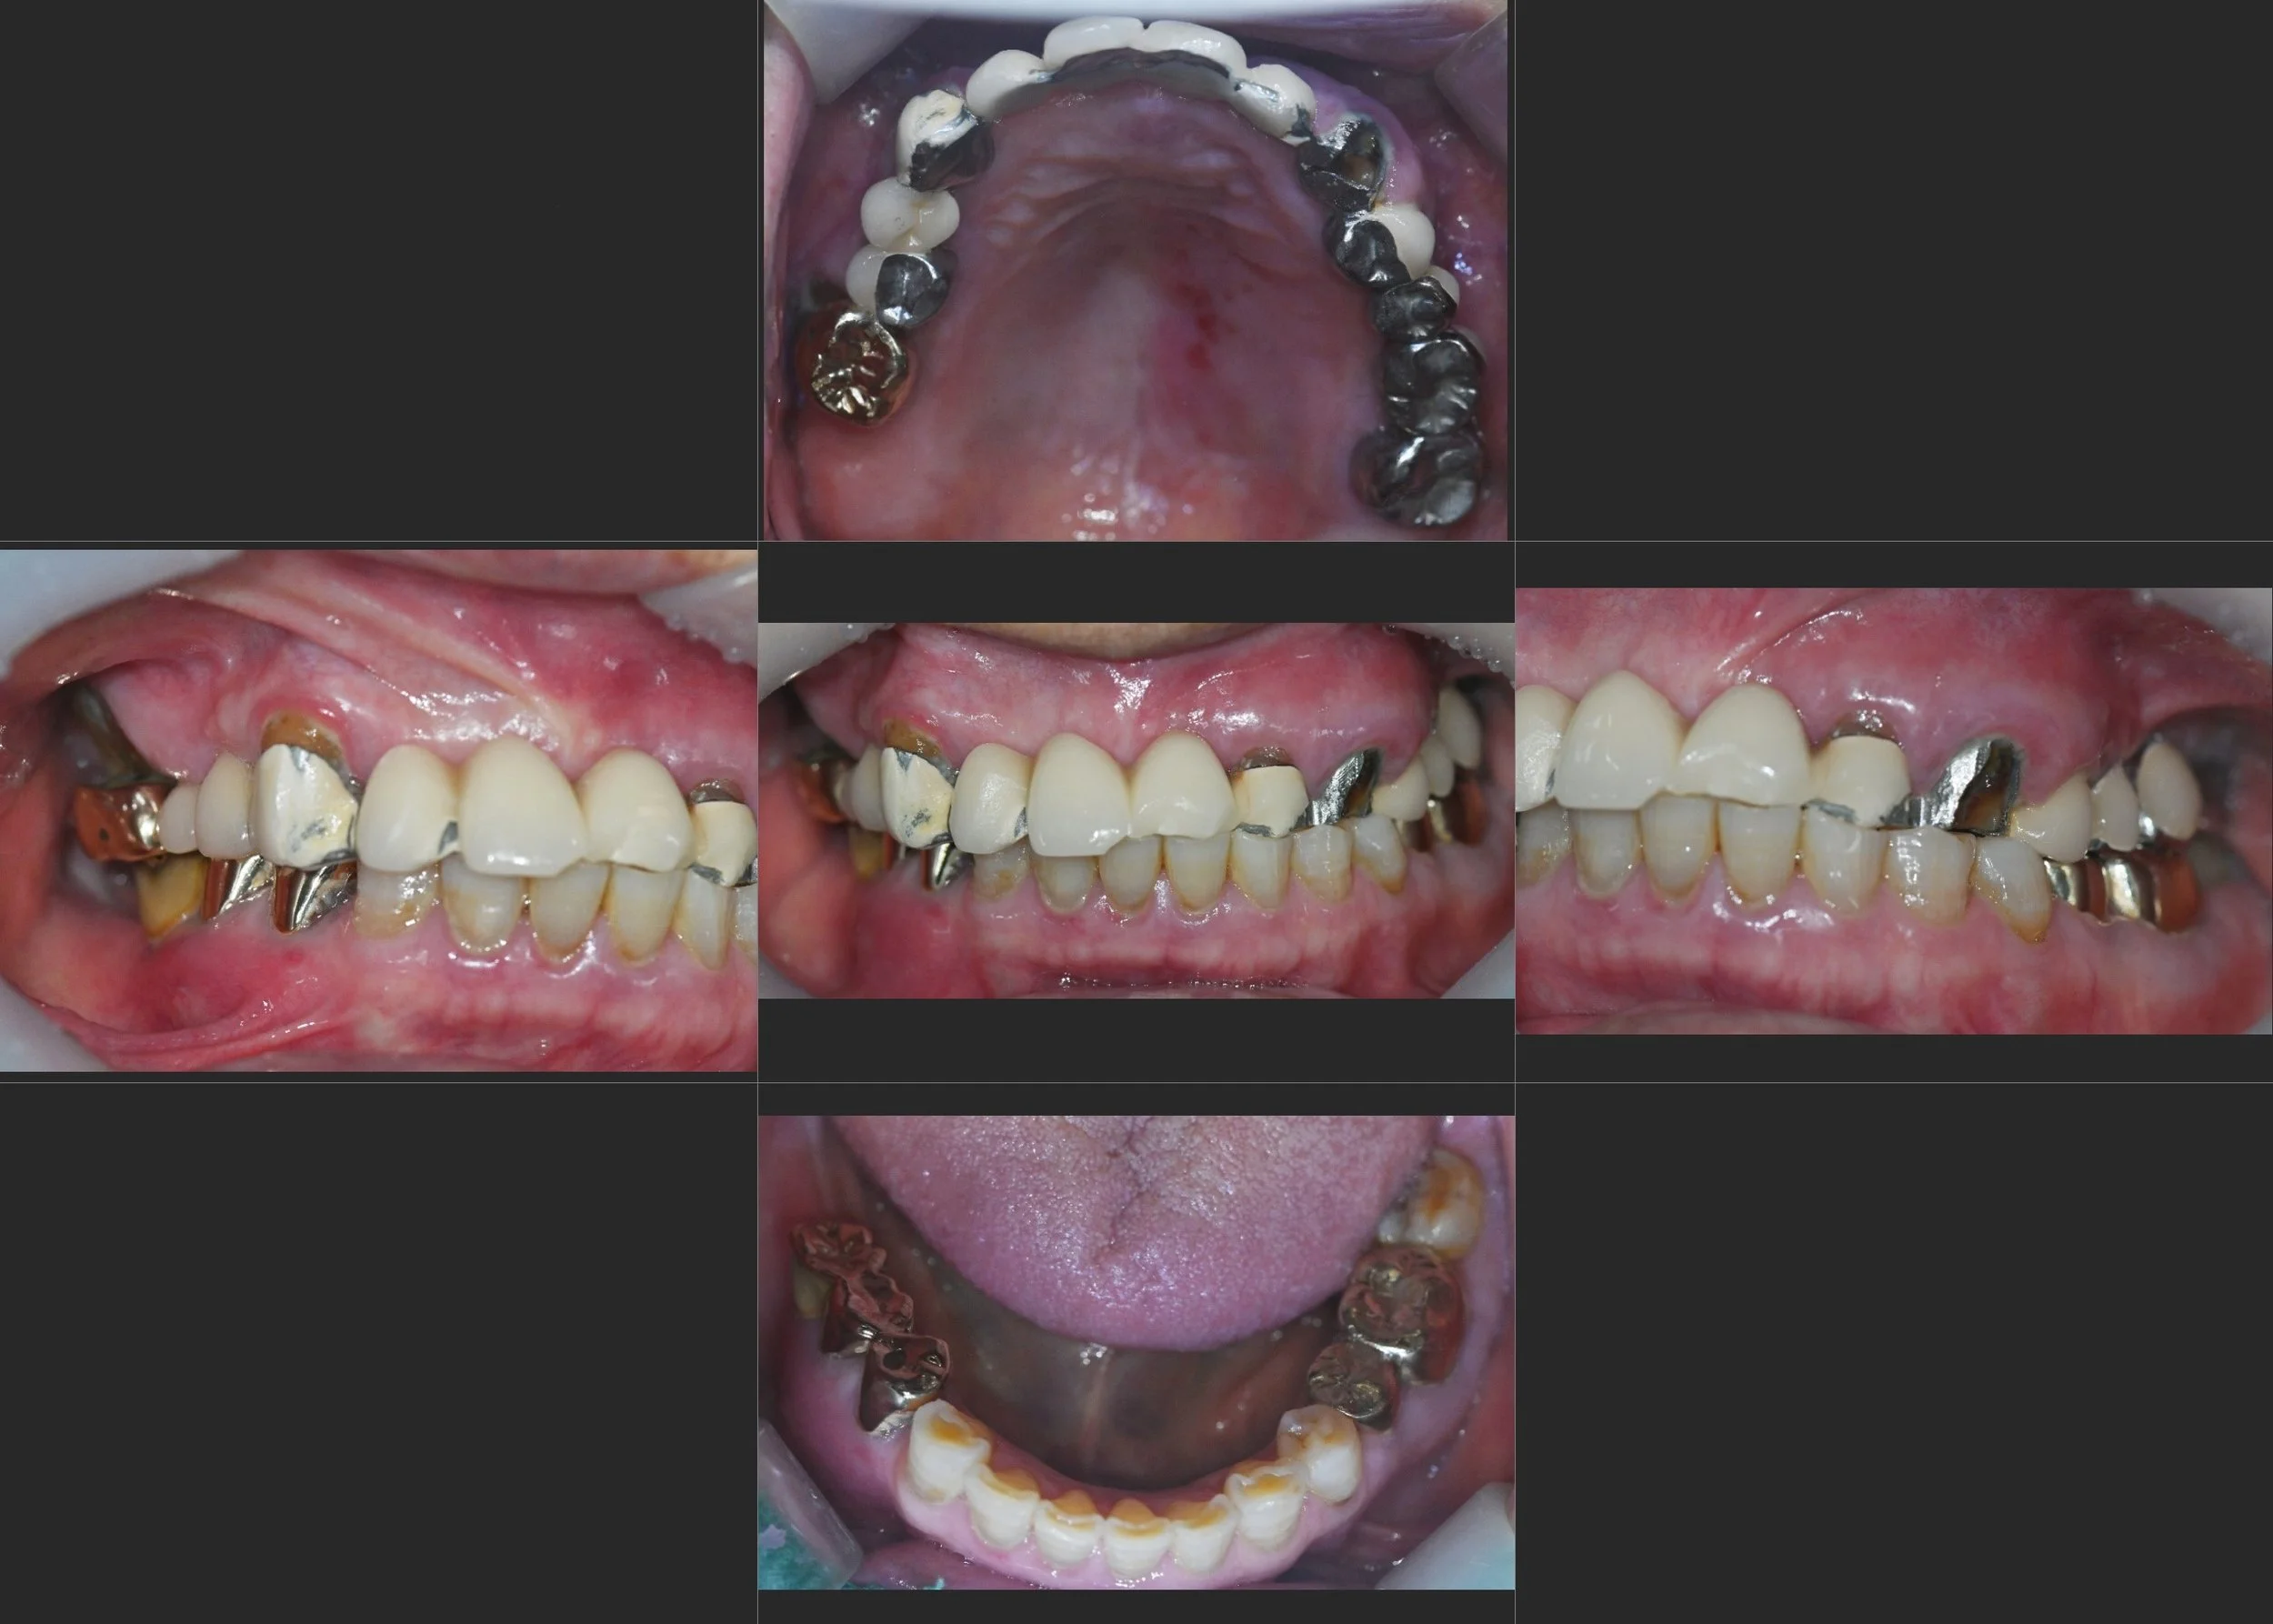

INTRA ORAL - BEFORE

The patient presented with repeated prosthetic fractures and progressive abutment tooth damage,

resulting from long-standing improperly designed restorations.

Incorrect bilateral occlusal height had caused mandibular deviation and a significant midline shift,

leading to functional instability and discomfort.